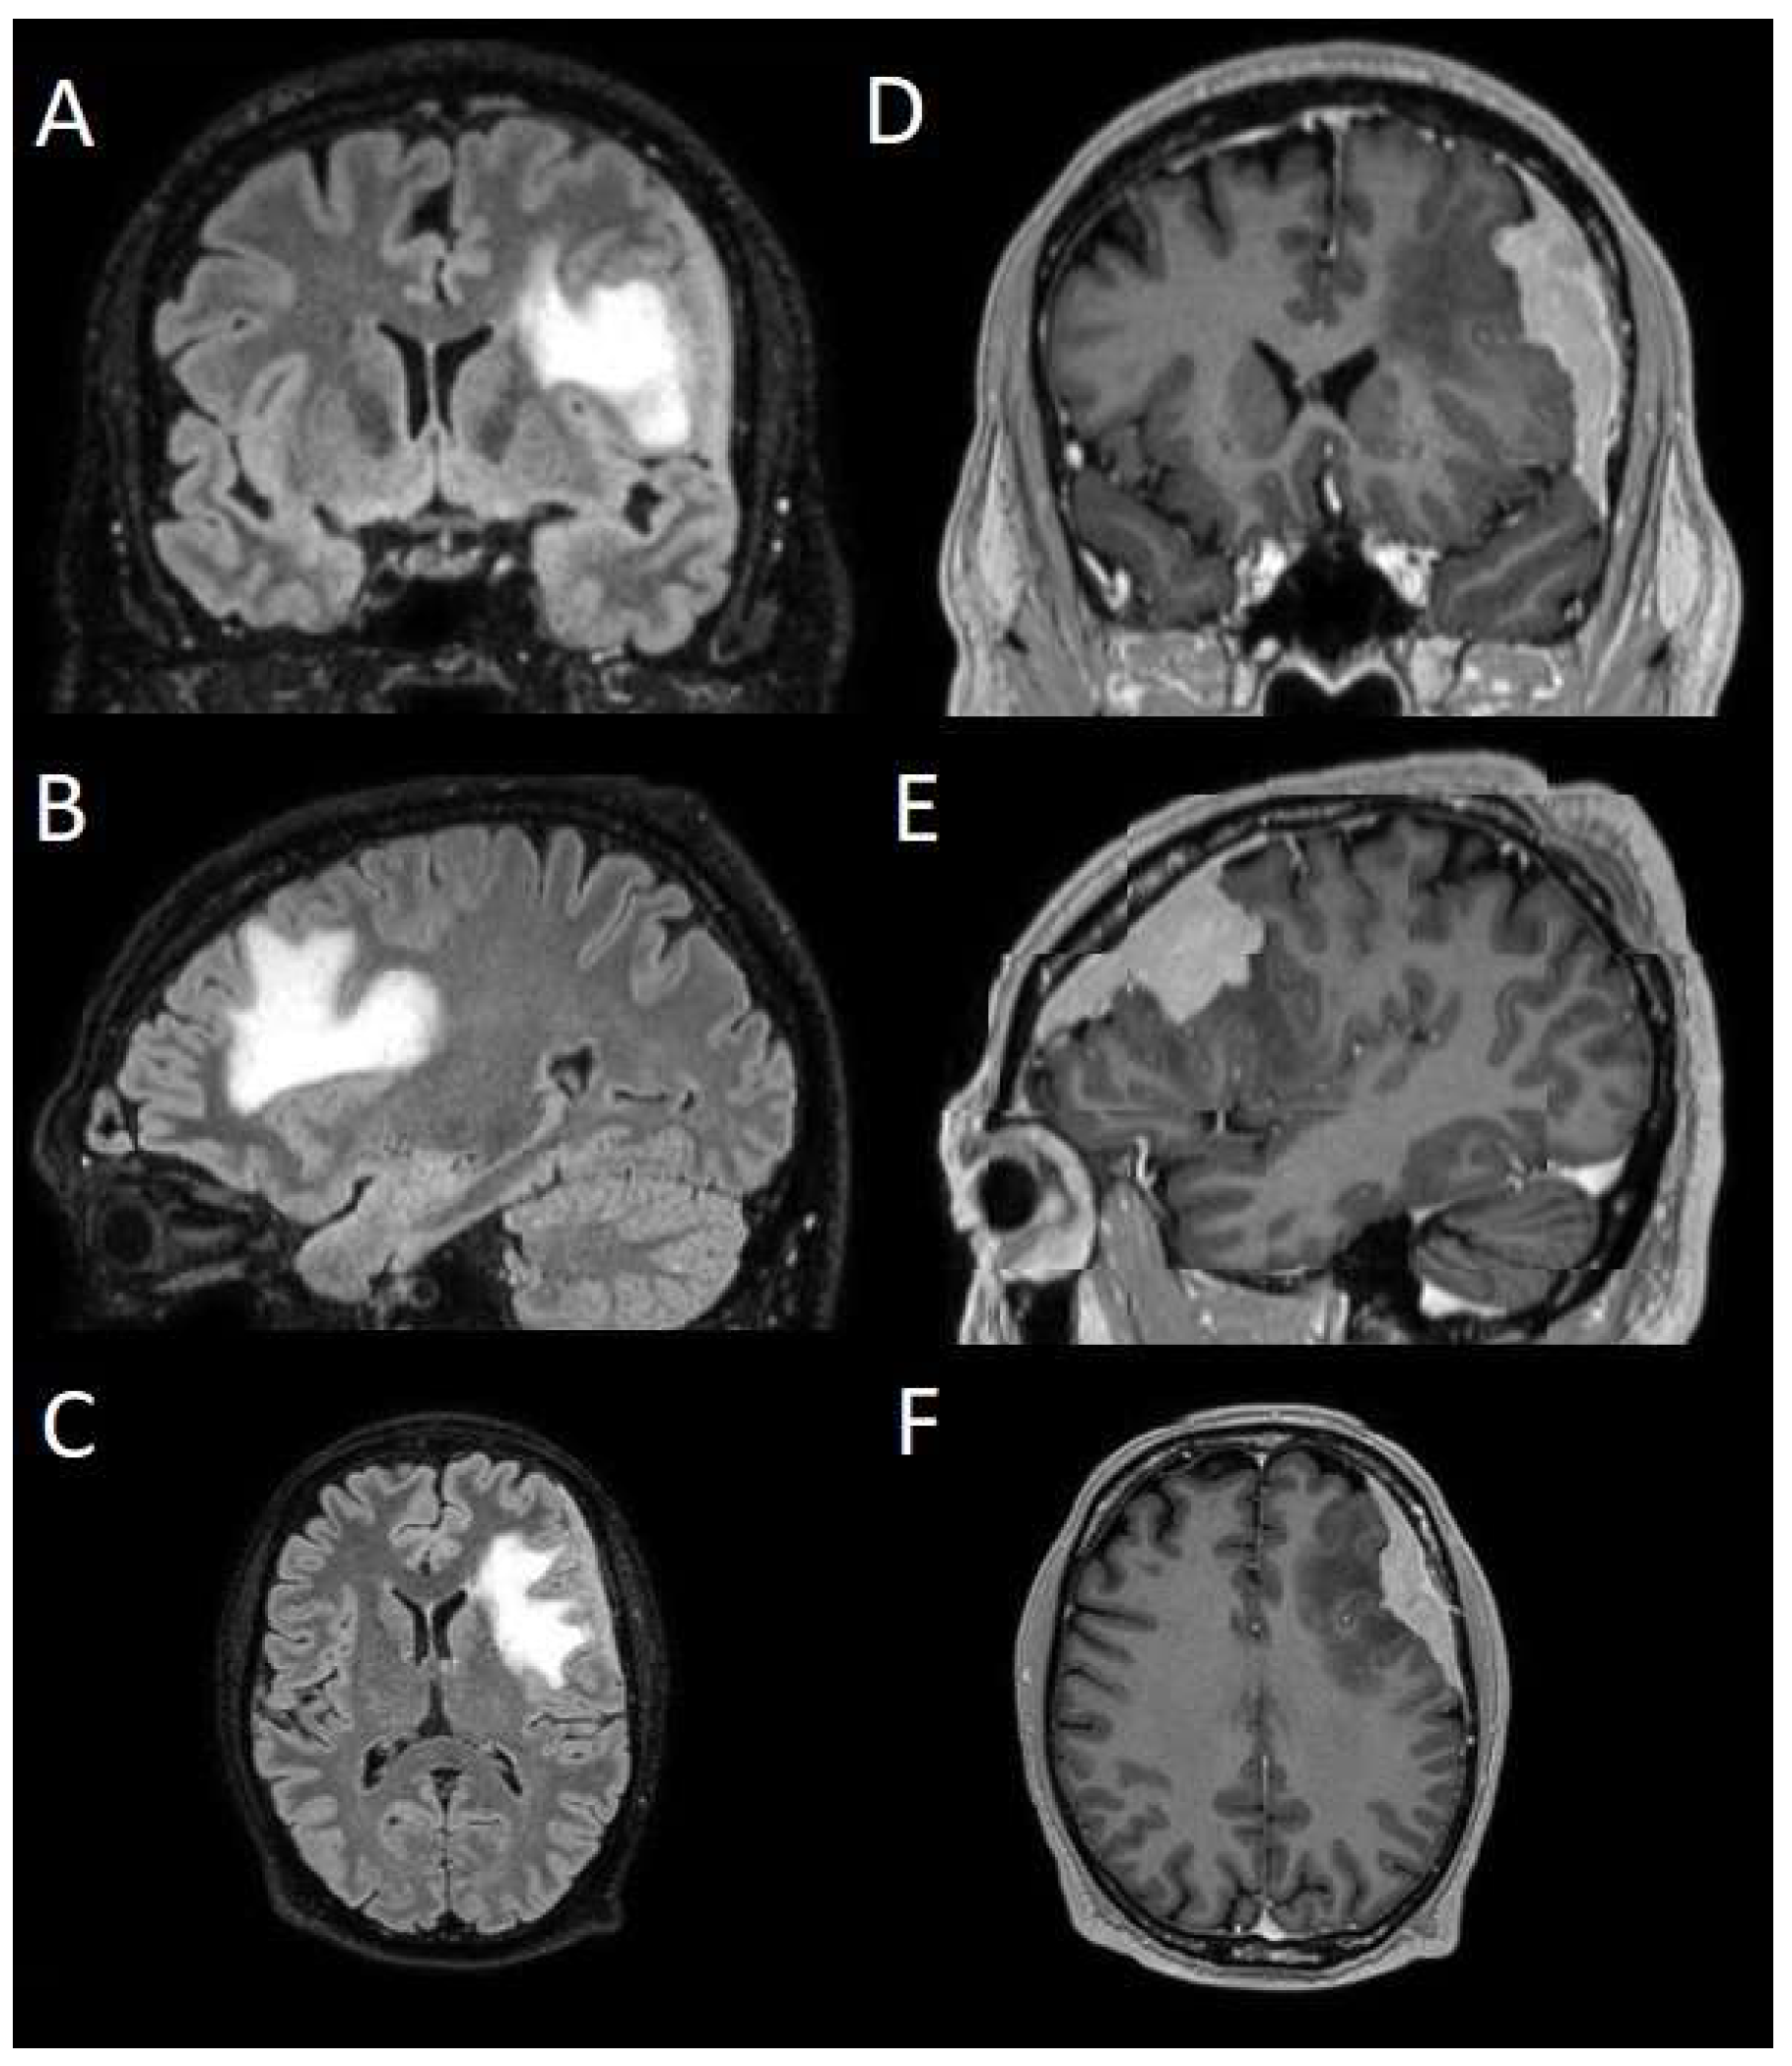

To evaluate which independent variables (meningioma volume, PE volume, the ratio between meningioma and PE volume, and the presence of preoperative epilepsy) influenced the dependent variable (seizure outcome), we performed a binomial logistic regression, which required converting continuous variables into binary values. For PE volume, values < 1 cm3 were coded as 0 (Figure 4), and values ≥ 1 cm3 as 1 (Figure 5). The cut-off was set at 3 cm3 for tumor volume, and for the volume ratio, the cut-off was 1. The absence of preoperative epilepsy was coded as 0, while its presence was coded as 1. Regarding seizure outcome, Engel IA cases were coded as 0, and cases classified as Engel > IA were coded as 1.

Figure 5. Segmentation process for PE > 1 cm3. (A,E) Automatic thresholding technique to identify initial regions of interest based on intensity values, respectively, for the PE and the meningioma. (B,F) Partially automatic erase of redundant signal with “erase outside” tool. (C) Precisely definition of boundaries of edema through manual erasure, cutting all around the redundant signal inside the tumor. (G) Manual erasing boundaries for tumor volume. (D,H) Final segmented volumes. PE: peritumoral edema.